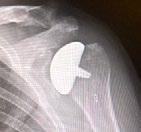

PHYSICIANSORTHOPEDICS

ADVANTAGE ORTHOPEDICS, INC

Dawn Allen 6670 Perimeter Dr. Dublin, OH 43016 614-526-2150 advantageorthodocs.com SEE AD ON PAGE 95